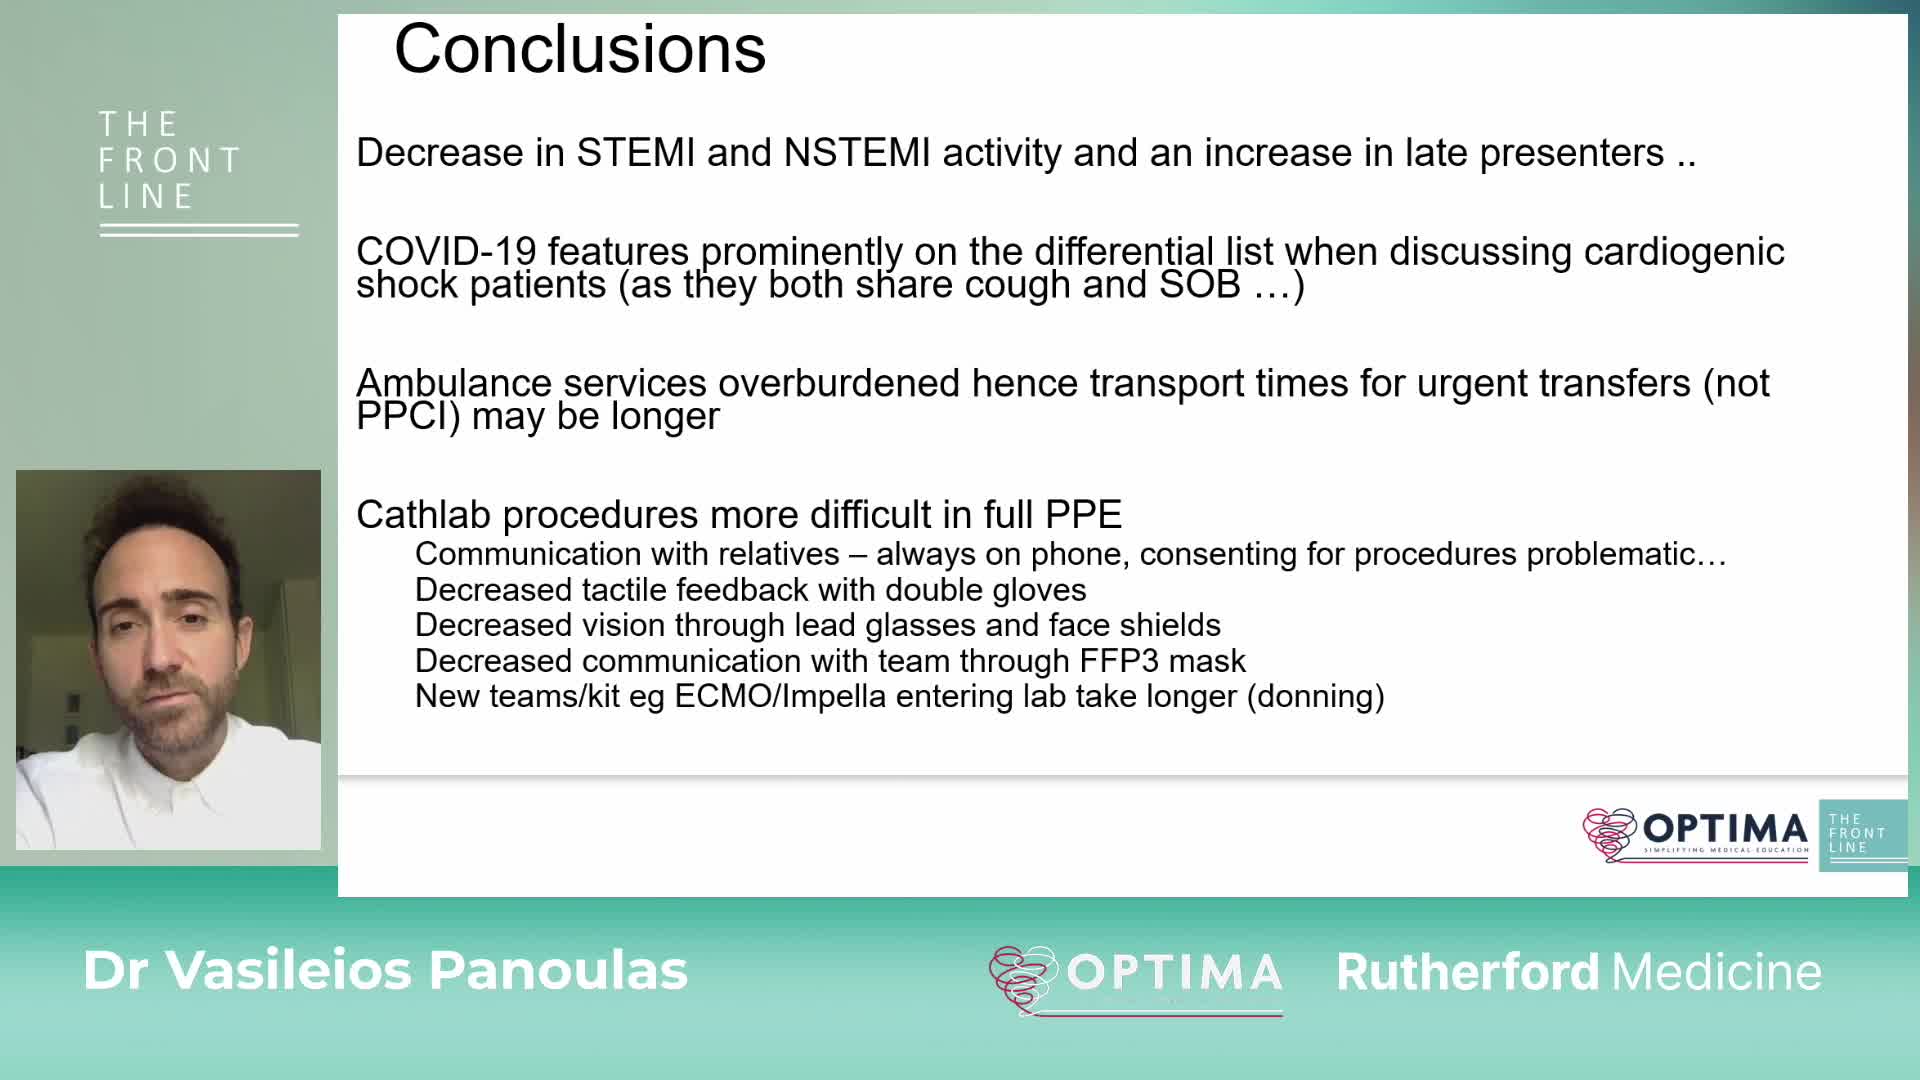

COVID-19: The Front Line. Challenges in treating high risk ACS cases in the COVID-19 era; a tale of a late infarct.